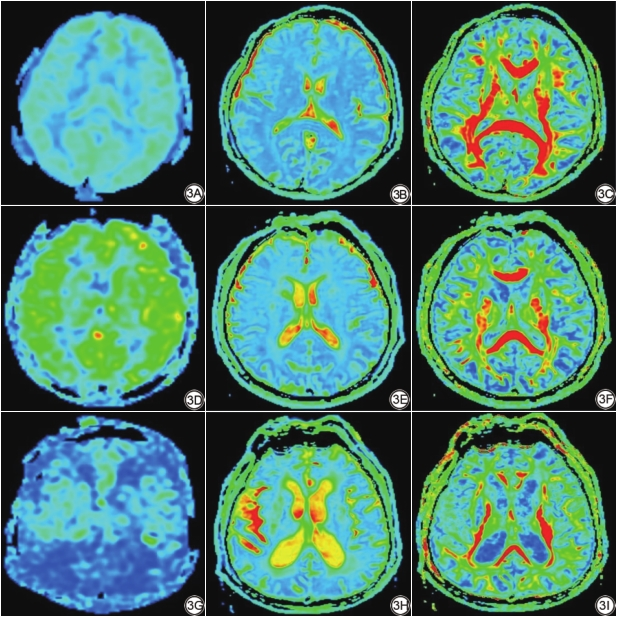

评价指标:(1)CBF反映大脑葡萄糖利用、耗氧、有氧糖酵解等功能代谢情况[15];(2)FA反映神经纤维的直径、密度、排列的一致性和髓鞘的完整性;(3)ADC反映水分子的扩散速度与范围(图3)。

相关性分析显示(图4),左侧额叶皮层下、右侧放射冠区、右侧半卵圆中心及双侧侧脑室前角、三角区周围正常脑白质区域的ADC值和CBF值呈负相关(r=-0.326,-0.21,-0.282,-0.443,-0.429,-0.357,-0.383),相关性最强的白质区域位于双侧侧脑室前角。双侧侧脑室前角周围NAWM区域的FA值与CBF值呈正相关(r=0.477,0.268),相关性最强的白质区域位于右侧侧脑室前角。